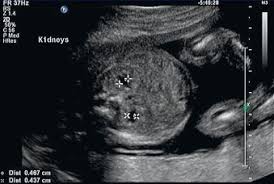

Trisomy 13 is often picked up at 12 weeks with an increased nt. Nosis of trisomy 18 to be made at the time of ultrasound examination. This is referred to as complete trisomy 13 or full trisomy 13. Overlap and difference in ultrasound findings trisomy 13 and trisomy 18. The amniocentesis came back positive for trisomy 13 (preliminary workup showed the abnormality in 97.5% of her cells). This is because each a. The most common abnormalities visualized are cardiac abnormalities, holoprosencephaly, omphalocele, and cleft lip/palate. Diagnosis of trisomy 13 on cvs should be followed up with amniocentesis and serial detailed ultrasound.

Now, this doesn't mean that the abnormalities aren't there. Trisomy 13 is typically due to having three full copies of chromosome 13 in each cell in the body, instead of the usual two copies. Patau syndrome (also known as trisomy 13) is considered the 3 rd commonest autosomal trisomy. Trisomy 13 and 18 are very different in terms of what you can see on ultrasound. Trisomy 13 represents the presence of an extra chromosome 13 resulting from a free copy or translocation. When an afp test indicates a high risk for trisomy 13, usually a level 2 ultrasound (also called a targeted ultrasound) is scheduled. The screening also determines risk of patau (trisomy 13) and edwards (trisomy 18) syndromes, rare and often fatal chromosomal abnormalities. If a maternal fetal dna test result comes back as high risk for a chromosomal abnormality, the recommendation (1) is to confirm the. Greater than 90% of fetuses with trisomy 13 have findings detected on prenatal ultrasound. Targeted sonography identified abnormal fetal anatomy or abnormal biometric measurements in 95% of fetuses with trisomy 13 in the second trimester after 17 weeks' gestation. Smith et al (1999) summarized the findings of 11 cases of trisomy 13 detected on cvs, of which, three cases had confirmed trisomy 13 mosaicism in the fetus. The purpose of this chapter is to focus on the evaluation and management of isolated ultrasound soft markers diagnosed in the second trimester. Fetal ultrasound during pregnancy can also give information about the possibility of trisomy 18 or 13, but ultrasound is not 100 percent accurate because some babies with trisomy 18 and 13 may look the same on ultrasound as those without the syndrome.

Identify major defects on the sonogram associated with trisomy 13. Fetal ultrasound during pregnancy can also show the possibility of trisomy 13 or 18. When ultrasound findings are consistent with trisomy 13, prenatal karyotyping should be undertaken. Greater than 90% of fetuses with trisomy 13 have findings detected on prenatal ultrasound. This is referred to as complete trisomy 13 or full trisomy 13. After completing this course, the participant should be able: Fetal ultrasound during pregnancy can also give information about the possibility of trisomy 18 or 13. But ultrasound is not 100% accurate. Fetal ultrasound during pregnancy can also give information about the possibility of trisomy 18 or 13, but ultrasound is not 100 percent accurate because some babies with trisomy 18 and 13 may look the same on ultrasound as those without the syndrome. The nt ultrasound is done between 11 and 13 weeks, when baby's nuchal translucency, the clear tissue located at the back of a developing baby's neck, can be measured. Targeted sonography identified abnormal fetal anatomy or abnormal biometric measurements in 95% of fetuses with trisomy 13 in the second trimester after 17 weeks' gestation. Smith et al (1999) summarized the findings of 11 cases of trisomy 13 detected on cvs, of which, three cases had confirmed trisomy 13 mosaicism in the fetus. Targeted sonography identified abnormal fetal anatomy or abnormal biometric measurements in 95% of fetuses with trisomy 13 in the second trimester after 17 weeks' gestation.